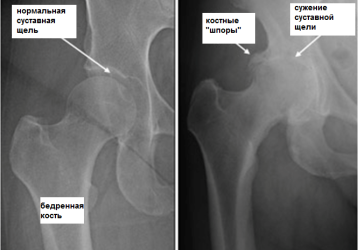

Что такое коксартроз тазобедренного сустава и как его лечить, симптомы, полное описание заболевания

Причины развития коксартроза тазобедренного сустава, характерные симптомы. 4 степени развития патологии, методы диагностики. Все способы лечения недуга. Профилактика заболевания.